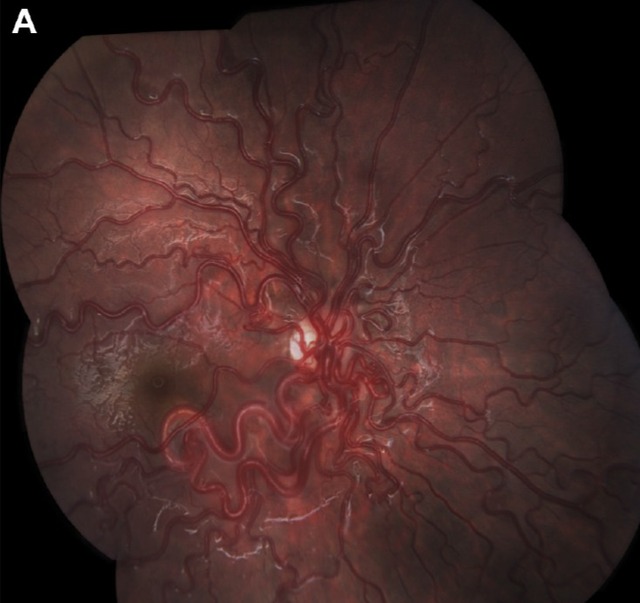

患者,男,6 岁,右眼视力光感,瞳孔对光反应缺陷,眼底照相显示扩张扭曲的眼底血管(图 A)。OCT 显示视乳头与黄斑间的视网膜下层有积液层(图 B 箭头处)。MRI 图像显示视神经管或眶尖有增强(图 C 箭头处),在后眼眶匍匐的小血管有流空现象(图 D 箭头处)。这些眼部与脑部的病理变化与 Wyburn-Mason 综合征有关。

图 C-D 为患者头颅 MRI 图像